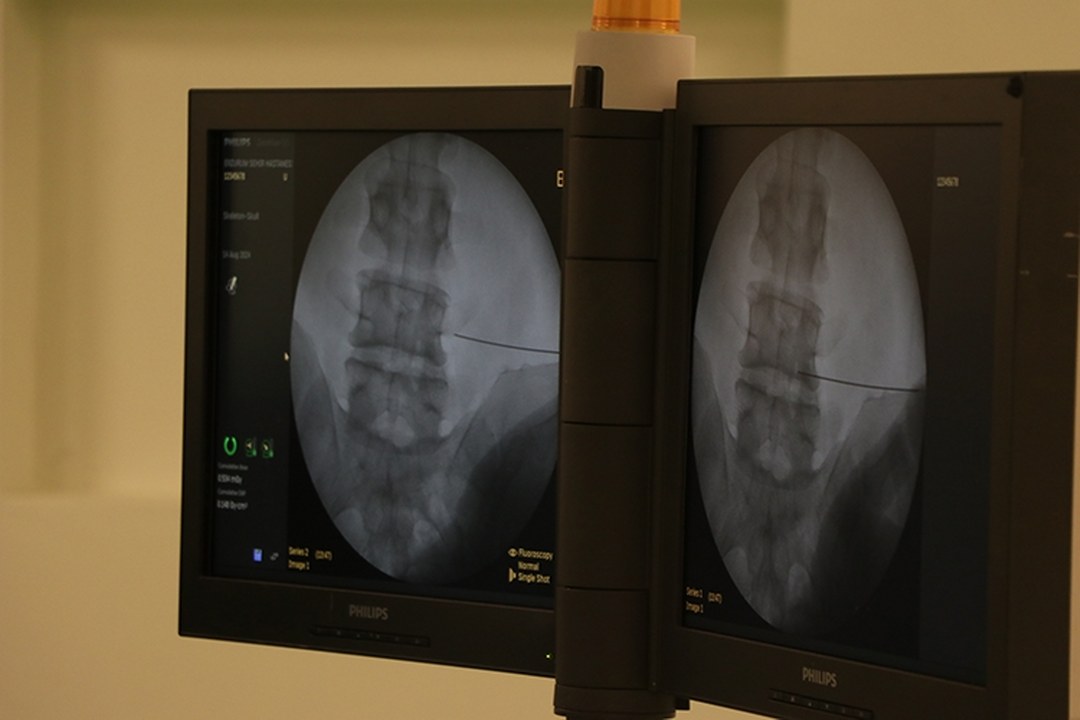

“Günümüzde fıtık ameliyatlarının açık ve laparoskopik (kapalı) yöntemlerle başarıyla uygulanıyor. Cerrahi yöntem hastaya özel olarak planlanıyor. Günümüzde fıtık ameliyatları son derece güvenlidir. Buna karşın fıtıkla uzun süre yaşamak ciddi riskler barındırır. Doğru bilgi, doğru zaman ve doğru tedavi hayat kurtarır.”